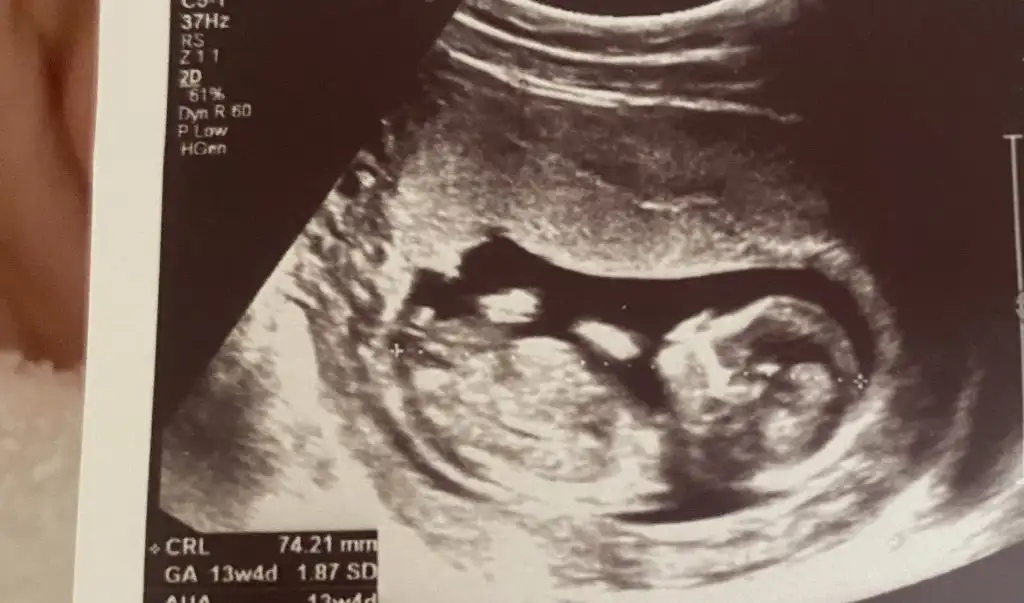

Canim bahar ergen cok iyidir gidebilirsen ona git yuzyil esra gunay oda iyiSelam ben yine doktordan geliyorum, Pendik’te aradığım doktoru hala bulamadım. Bugün medipolde gittiğim doktor çok ilgisizdi cinsiyeti geçen hafta kız diye söylemişti başka bir doktor bu doktorda 11. Haftada cinsiyet mi oluyormuş da söylüyormuş diye diğer doktora laf etti. 16. Haftada anca söylenilir dedi. Kadın beni çok gerdi gerçekten zor geçiyor benim için

Hayirli olsun canim senin adina sevindim banada dr soyledi cinsiyeti ama ben emin olmak icin bekliyorum senden sonraCanım benim bebeğimin cinsiyetini güncellerimisin kızım olacak Allah nasip ederse![]()